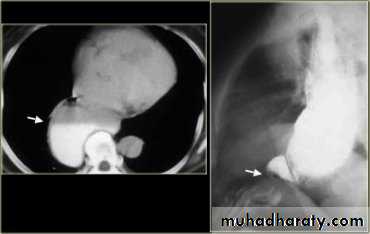

Sliding herniaOn the left initially, GE junction is below the esophageal hiatus. Later, stomach protrudes through hiatus

Para esophageal hernia

On the far left gas filled gastric funds (asterisk) protrudes through hiatus but GE junction (arrow) is below diaphragm• Thin mucosal fold (membrane)